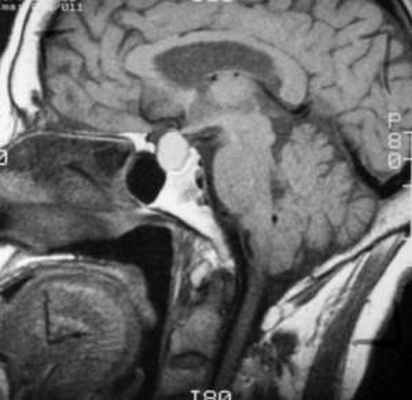

На изображениях ниже можно посмотреть, как киста Ратке выглядит на снимке .

МРТ: киста кармана Ратке. На Т1-взвешенном сагиттальном изображении, полученном до введения контраста, заметно четко очерченное образование в области турецкого седла – с распространением в супраселлярную цистерну. Отмечается гомогенно высокая интенсивность сигнала в образовании по сравнению с паренхимой головного мозга.